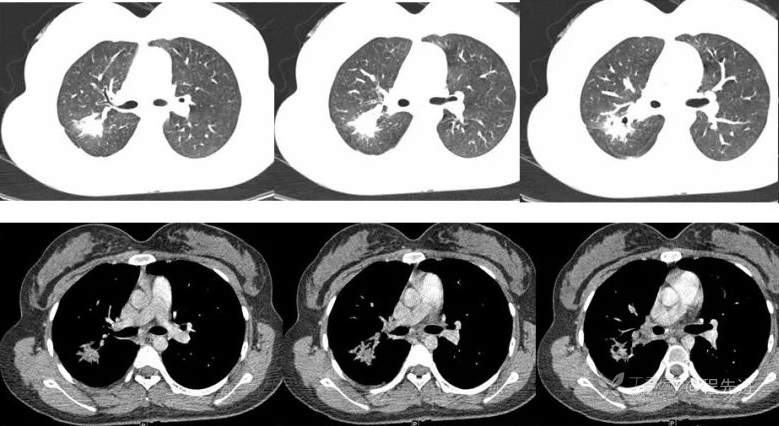

简要病史:患者体检发现右上肺不规则结节影,周围可见小结节影,右肺门及纵隔内多发肿大淋巴结影,当时患者临床无明显症状,支气管镜检考虑结核可能性大。完善T-SPOT阳性,予以诊断性抗结核治疗,肺部病灶吸收好转,9个月后在当地医生指导下停药。

又3个月后,患者停药后复查,右上肺结节较前明显增大。现为进一步诊治,遂于今日来我院就诊。

抗结核治疗后,复查